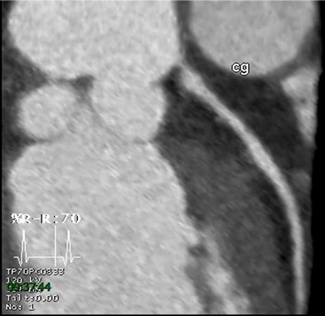

A 41-year-old Asian woman was presented with out-of-hospital cardiac arrest. As she was in a musical concert, she presented a sudden cardiac arrest (SCA), she had immediate chest compression by attending first-aid workers, with a no-flow of less than 2 minutes. Spontaneous circulation was restored after 4 minutes of cardiopulmonary resuscitation and 2 electric shocks. Hemodynamics was stable with no need for inotropic support and electrocardiogram showed sinus tachycardia without repolarization abnormalities. At hospital admission, the scan eliminated recent intracerebral bleeding and pulmonary embolism. Then a coronary angiogram revealed a chronic total occlusion of the ostial left main trunk with complete collateralization by the right coronary artery (Figure 1) (videos in supplemental material). The echocardiography showed no impairment in the left and right systolic function. After review, the CT scan showed increased thickness of the aortic wall of the thoracic aorta extended to the arch branches (Figure 2).

Figure 2: Initial CT scan showing circumferential thickening of the aorta.